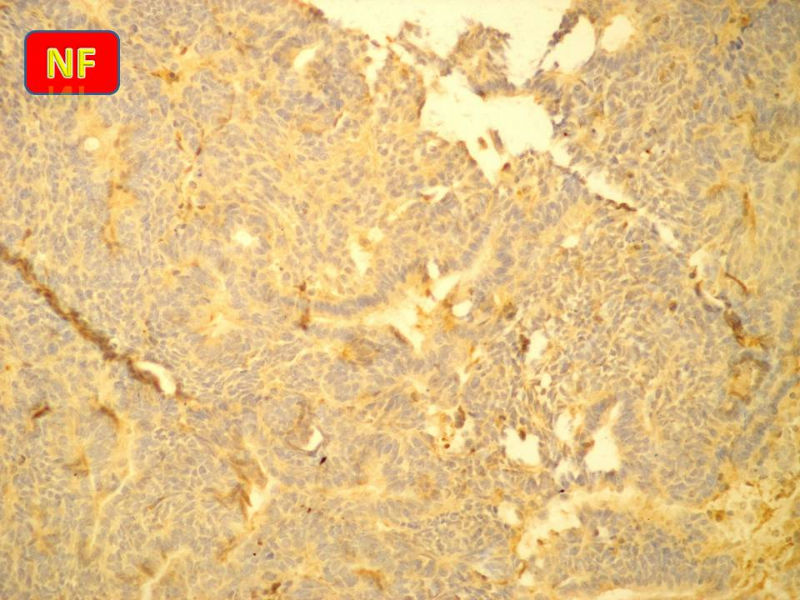

免疫组化S-100的阳性区域方式...嗅母可能性大。

1)嗅神经母细胞瘤?

腺肌上皮癌

支持嗅神经母细胞瘤(伴有腺体分化)